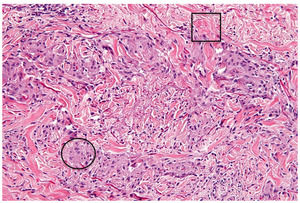

Contemplating the possible etiologies of this rash, the second author (MS) of this report obtained punch biopsies from a papule on her left posterior shoulder, a patch on her left flank, and a patch on her left thigh. All biopsies showed similar findings: a dense infiltrate of histiocytes forming palisading granulomas within the upper dermis. The epidermis did not show any atypical lymphocytes. Necrobiosis of connective tissue material was also appreciated (see Figure 3).

These histopathologic findings, in accordance with the patient’s history and physical exam findings, confirmed a diagnosis of patch GA. The patient was prescribed topical betamethasone dipropionate 0.05% ointment twice daily, which is a more potent steroid than her previously used triamcinolone 0.1% cream. Weekly UV phototherapy was also recommended. However, the patient elected to proceed with topical therapy only as it would be too challenging to present for regular UV treatments give her home situation.